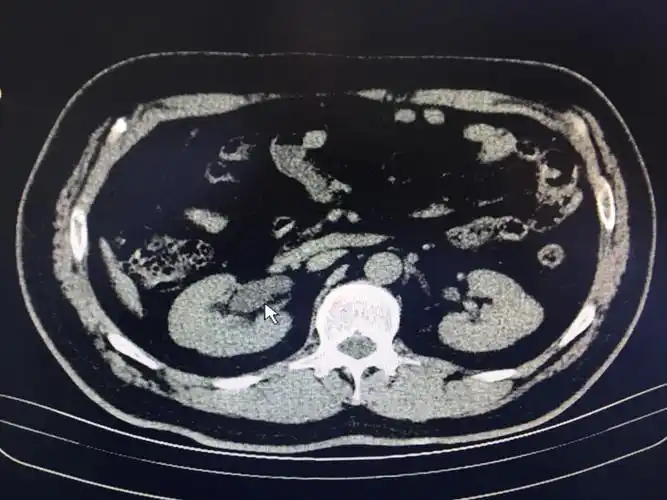

腹腔积液的良恶性表现与鉴别

3个病例8副图带你读懂腹水